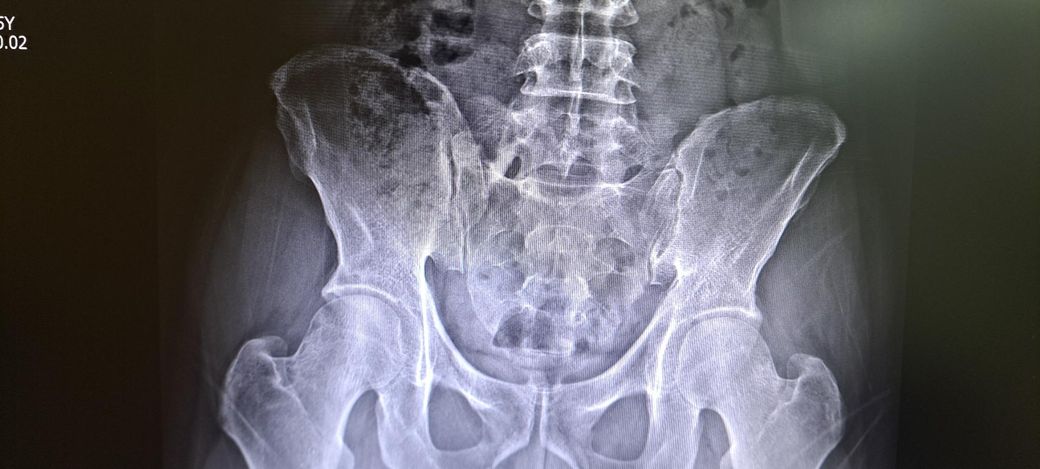

x ray 촬영한 영상인데 골반 틀어짐 및 전방경사 심각한가요? 골반 틀어짐은 어느 쪽을 교정해야 하며 골반 틀어짐 및 전방경사 교정 방법을 알려주시면 감사하겠습니다 .

일단 골반 같은 경우 좌우 대칭이 다르며 약간의 전방 경사 및 틀어짐이 있는 것으로 보입니다.

정면 사진상 골반의 좌우높이 차이가 관찰되며, 이는 대퇴골의 위치변화와 연관되어 보입니다. 측면 사진에서 요추의 곡선이 다소 꺾여 있는 양상이 보여 골반 전방경사 가능성이 큽니다. 정면 영상에서 척추가 일직선이 아니라 완만한 S자 형태로 휘어있는 측만 소견이 보입니다. 심각한 수준은 아니나 지속적인 관리가 필요한 상태입니다. 측면 사진상 경추의 커브를 보면 일자목 상태입니다. 골반이 높은쪽의 근육은 이완시키고, 낮은쪽과 약해진 둔근, 복근을 강화하는 운동이 필요합니다. 전방경사 완화를 위해 장요근 스트레칭과 프랭크 같은 코어 운동이 효과적입니다. 흉쇄유돌근 스트레칭과 더불어 등 근육을 강화하여 어깨를 펴는것이 급선무입니다.

골반 틀어짐을 보면 오른쪽 골바 날개가 왼쪽보다 높이 위치한걸 볼 수 있습니다. 하지만 이 사진만으로 판단하기보다는 발끝까지 찍은 사진을 보고 왜 오른쪽 골반이 더 위로 높아져있는지를 판단해야 원인과 해결법을 판단할 수 있겠습니다.

척추측만은 의미있는 정도가 아닙니다. 저희가 20도 이상을 증상을 유발할 수 있는 측만으로 보는데 그만큼 측만이 확인되지 않습니다.